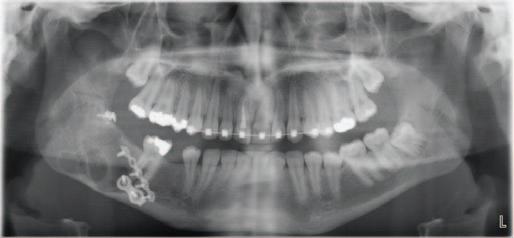

A 30-year-old patient presented to your clinic complaining of a discoloured front tooth (Figures 1 and 2). There was no pain or other symptoms associated with it and it has become increasingly discoloured over time.

1. What is the likely reason for this type of discolouration?

2. What special tests do you perform as part of your exam?

3. What are the potential sequalae for this tooth?

4. What are the possible treatment options for

this tooth and what are the potential difficulties with doing a root canal treatment?

Answers on page 45.

FIGURE 1: Patient presenting with discoloured front tooth. FIGURE 2: Periapical radiograph 1.